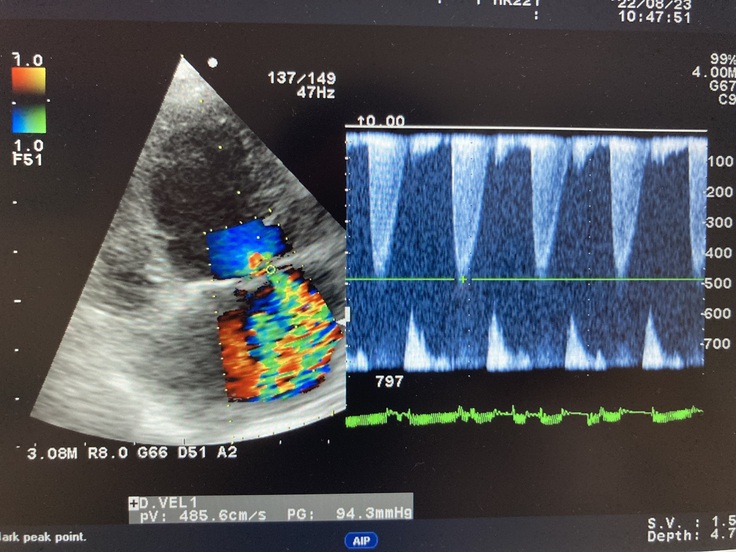

▼現在のココのレントゲンとエコー写真

心臓が大きく肥大していて

逆流も多く、かなり悪い状態で

余命6〜9ヶ月と宣告されました。